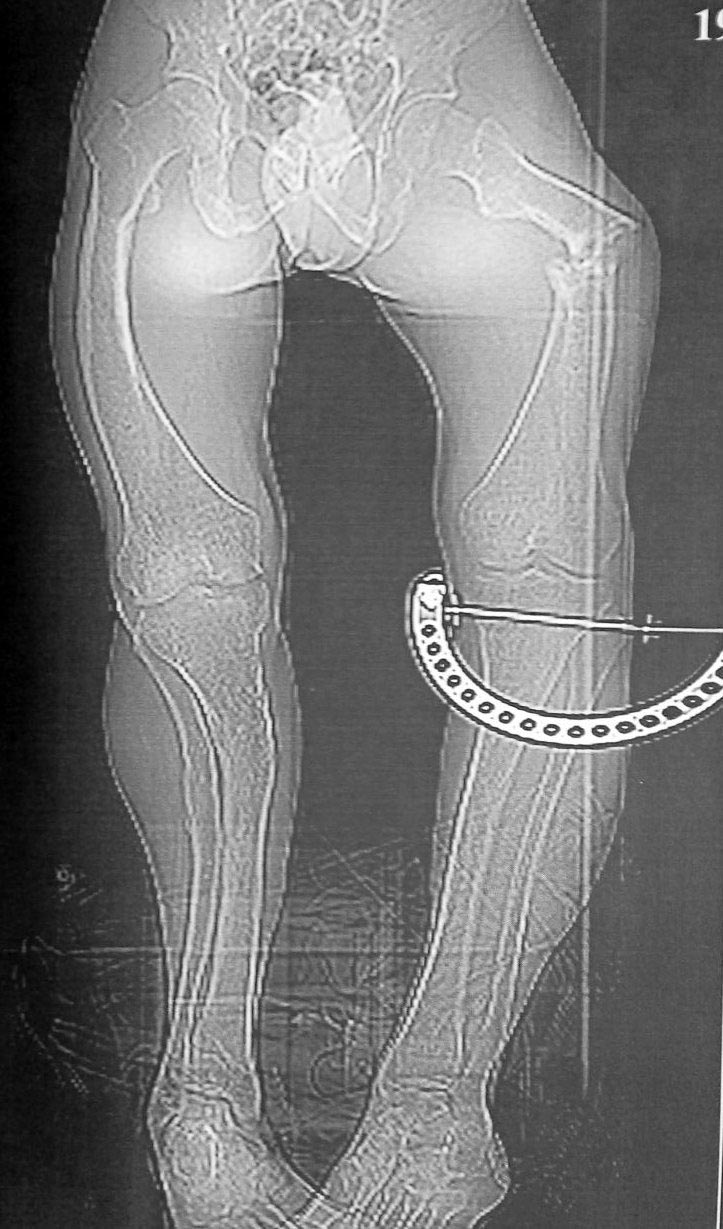

Помогите разобраться с переломом бедра у непростого пациента.

Молодой пациент (абсолютно социален и адекватен), рост около 140 см,

бедро 20 с небольшим, по механической оси. Низкоэнергетическая травма,

судя по записям в амбулаторной карте - несколько раз оперировался по

поводу болезни Блаунта в детстве на голенях, сведений и следов

операций на бедрах нет. Рассматриваем несколько вариантов остеосинтеза:

3. ЧКО Нужно ли резецировать зону перелома при последних двух вариантах

(выглядит как псевдоартроз)? Любые соображения, варианты приветствуются,

сожалею за снимки, лучше не получилось.